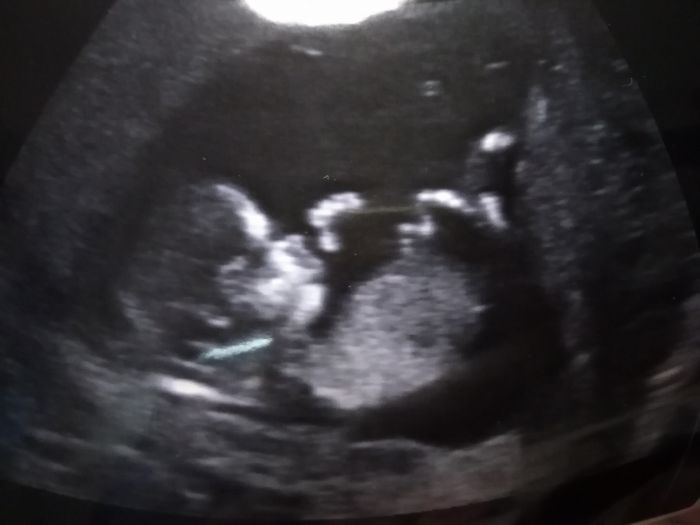

...pohlavi taky neřekl,prcek moc nechtel spolupracovat,byl otoceny zady,musela jsem se jít projit a teprve pak bylo jakžtakž neco vidět,ale pohlaví prý ne

Tak kdyz ti nebudou volat,bude vse v poradku,ne?Nebo bych zavolala sve gynekolozce a zeptala se ji. Nase mimco bylo videt dobre,rekl nam ze vysetril vse i pohlavi na rekl,ale jen na 70%,ono se to asi jeste blbe poznava.Ale cele vysetreni trvalo par minut. V ordinaci jsem byla max 10 min,prislo mi to dost rychle. Jak dlouho to trvalo u tebe?

) taky tak deset minut,miminko ma ted 7cm a jsem 12+5...no,rikal,že když bude vše v poradku,tak volat nebudou a výsledky poslou memu gynekologovi. Jak bylo velké vaše miminko?